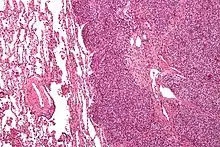

Histopathology

There are typically many small cells of the same size and appearance, with round nuclei.[3] Around half have extensive glycogen deposits, demonstrated with positive PAS staining.[3] Around 85% of Ewing sarcomas are positive for CD99, a cell-surface glycoprotein.[1] However, CD99 also occurs in some normal tissue and in other round cell sarcomas, as well as in lymphoblastic lymphoma and leukemia.[3] There may be keratin expression.[1]

Micrograph of a metastatic Ewing sarcoma with the characteristic cytoplasmic clearing on H&E staining, which was showing to be PAS positive

Micrograph of a metastatic Ewing sarcoma with the characteristic cytoplasmic clearing on H&E staining, which was showing to be PAS positive